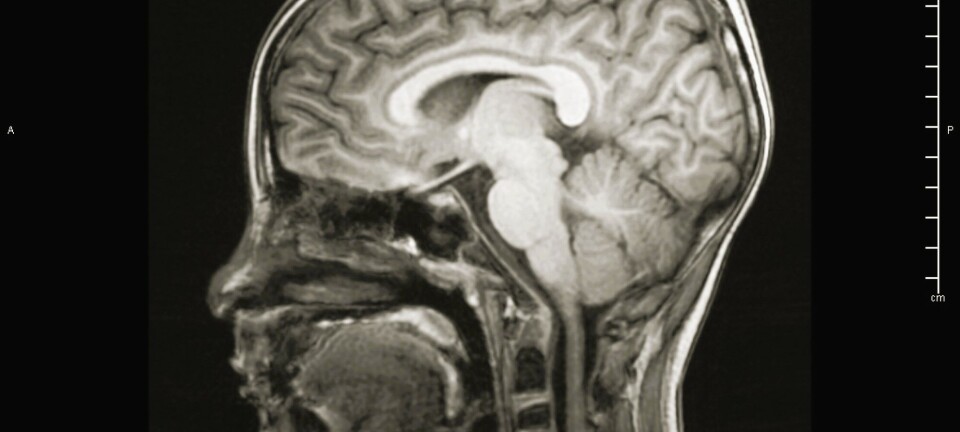

Fjell and his colleagues are trying to understand how the brain develops over our lifespan. They have based their work on research from thousands of MRI images of the brains from roughly 3,000 healthy Norwegian people from 0 to 100 years of age.